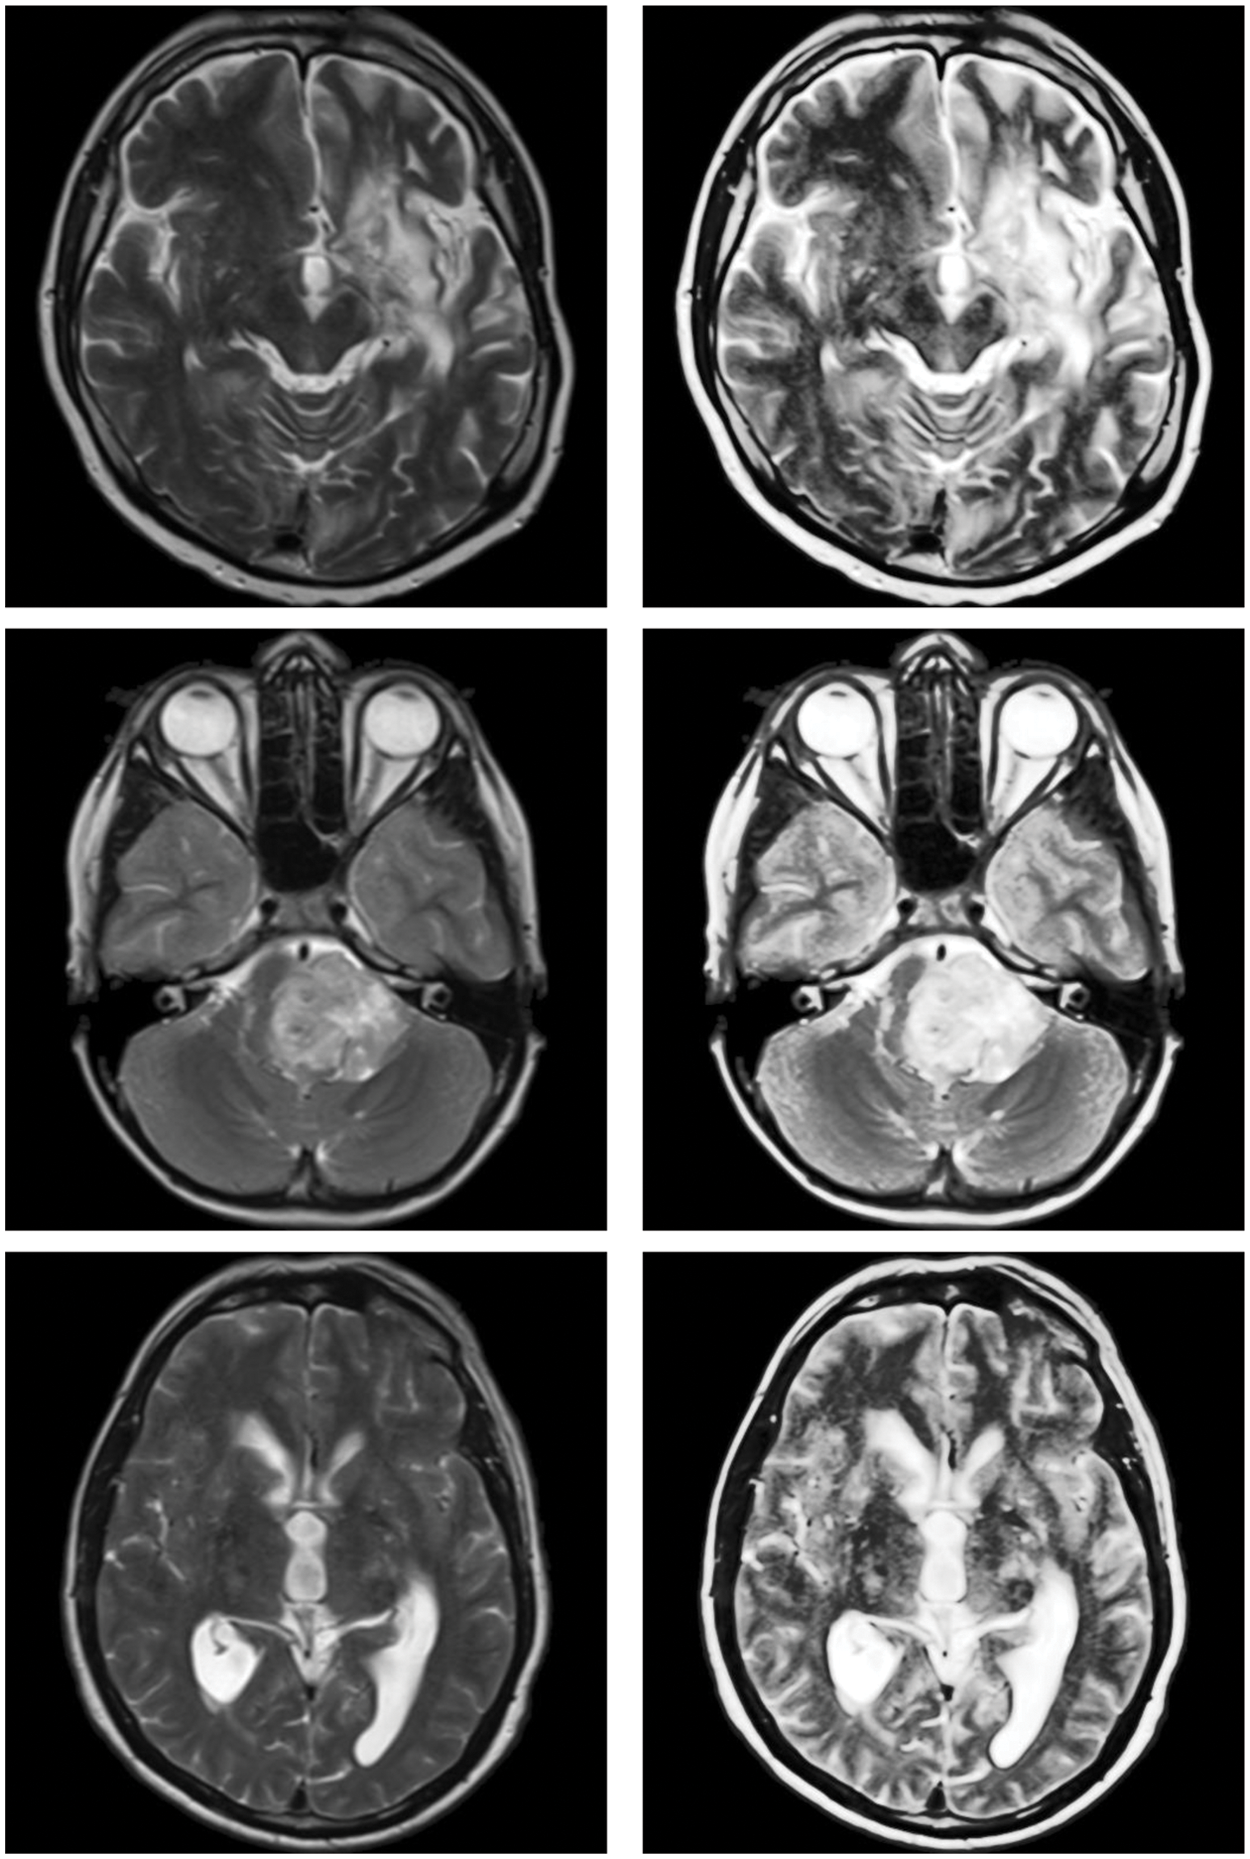

In Fig. 2, the proposed image enhancement techniques’ qualitative outcomes for MRI images are shown in which all the images exhibit various trends with dark and bright parts.

Figure 2: Sample inputs/outputs of the proposed algorithm

Overall, the proposed model’s produces the structures of medical images, which often depict edges, clearly specified. This is due to the model’s capacity to efficiently capture high frequency features. For images that are poorly lighted, the proposed approach produces reasonable visual results. This is the quantum calculus with q, and w parameters contribution to this study.